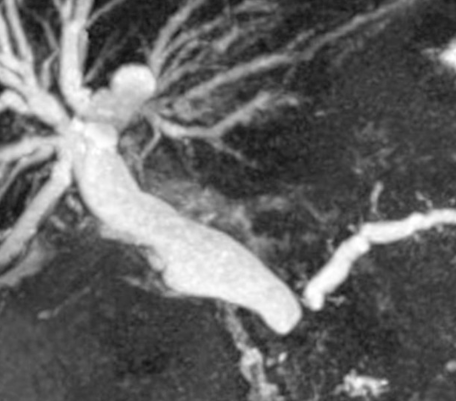

IRM

- Bonne détectabilité en T1 FS et T1FS Gd+ (parenchyme plus intense que le foie)

- le pancréas dilaté en amont, atrophique, sera de signal T1 plus bas

- Hypointense avec prise de contraste tardive

- Pas génial en artériel en IRM (le pancreas est hypervasculaire)

- Restriction de diffusion (mais n’aide pas trop car d’autres choses restrictent, comme les pancréatites autoimmunes)

- Cholangio-IRM: cutoff abrupt du cholédoque